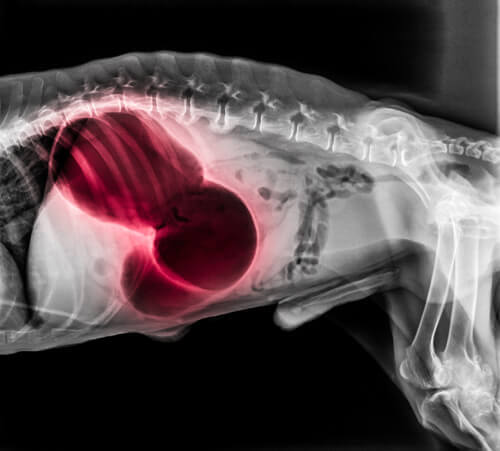

Região do coração ou pulmões

Nessas regiões, um coágulo pode levar a uma variedade de sintomas sistêmicos muito graves. Entre eles, pode haver desmaios, falta de ar e paralisia. Pode acontecer das gengivas ficarem pálidas ou azuis, incapacidade de dormir ou tosse com sangue. A embolia pulmonar costuma ser fatal.